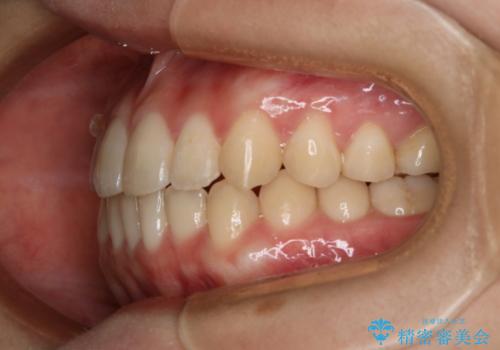

八重歯とクロスバイト:インビザライン治療

- 八重歯が気になるとの事でご相談にいらした方です。

インビザラインで綺麗に並べました。

気になっていた八重歯が綺麗になって大変喜んでいただけました。